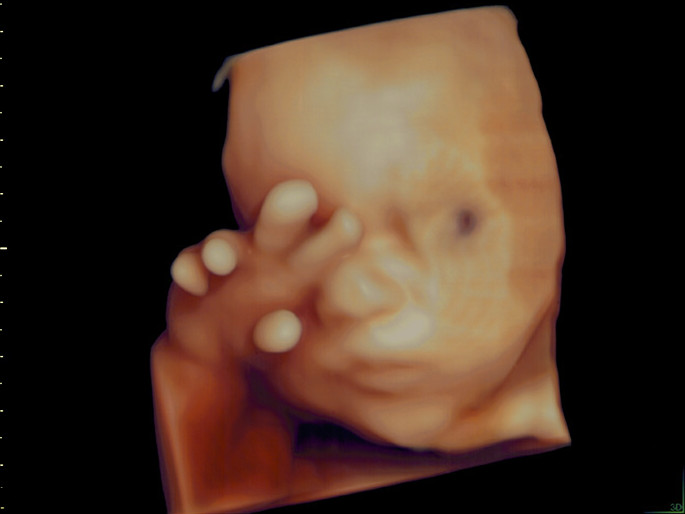

Unter der Pränataldiagnostik (= vorgeburtlicher Ultraschall) werden alle Untersuchungen in der Schwangerschaft zusammengefasst, die die möglichst genaue Beurteilung des ungeborenen Kindes ermöglichen, die frühzeitige Erkennung von Störungen der Entwicklung des ungeborenen Kindes sowie von Schwangerschaftsrisiken der Mutter. Diese Untersuchung wird auch als Fehlbildungs-Ultraschall bezeichnet. Sie wird mit einem hochauflösenden Ultraschallgerät durchgeführt. Damit können bereits in der Frühschwangerschaft viele Organe nicht-invasive beurteilt und untersucht werden.

Die vom Schallkopf ausgesandten Ultraschallwellen werden von den Körperschichten des Kindes reflektiert. Aus den zurückgesandten Schallwellen kann zweidimensionales Ultraschallbild berechnet werden. Dies ermöglicht die Darstellung der kindlichen Organe und die Erkennung möglicher Veränderungen.